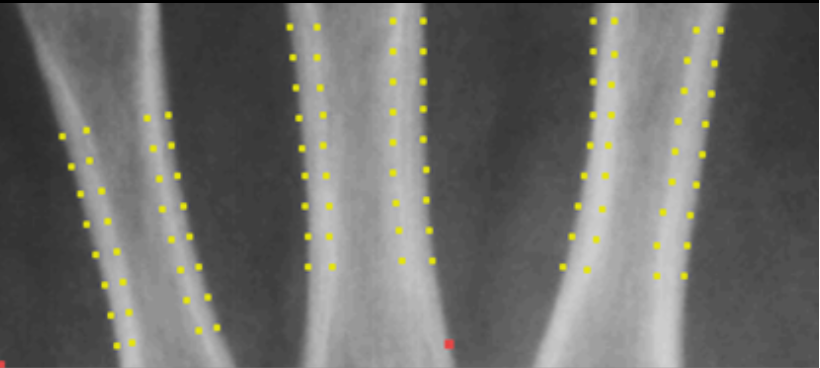

BoneXpert explains the overall bone age as the averaging over the annotated bones, like a human rater would do.

For each bone, BoneXpert displays the boundary, which substantiates the analysis, e.g. the relative width of the epiphysis is a crucial maturity indicator.